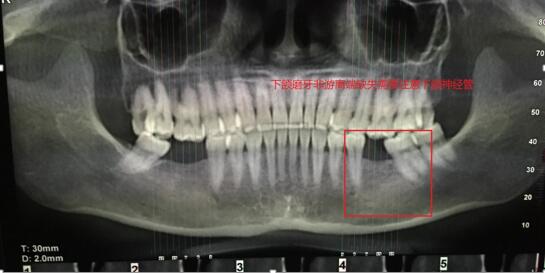

案例二:下頜前牙缺失